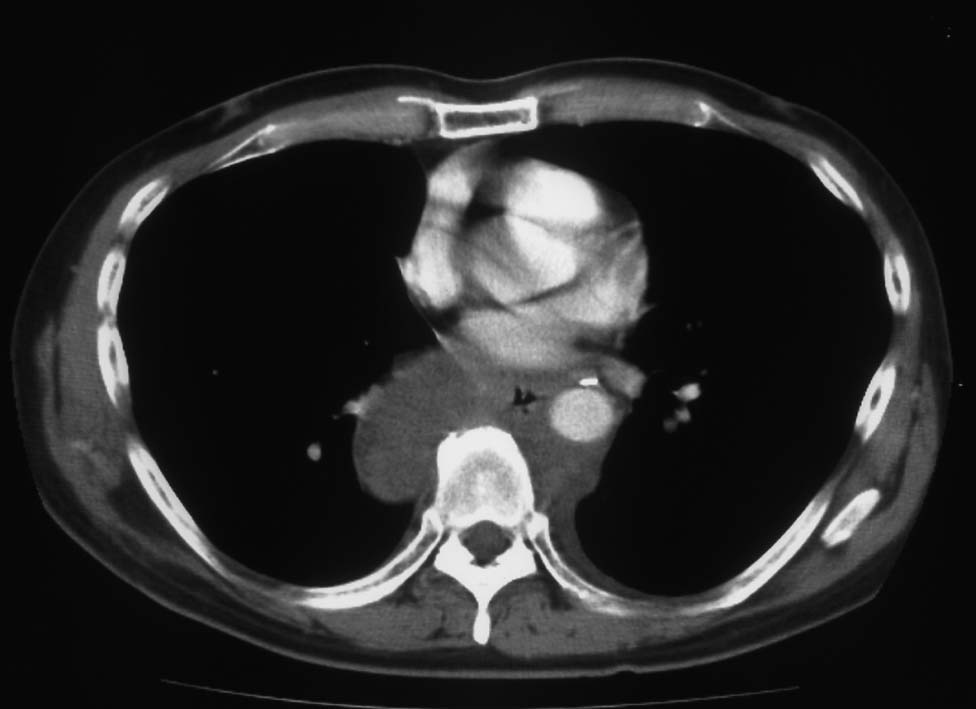

胸腔鏡下ブラ切除術5ヵ月後, 縦隔腫瘤で再発. 他院で腫瘍切除+右肺上葉切除を施行. 肉眼的には腫瘍は完全に切除できた.

病理診断は, 非典型的所見ながらmalignant solitary fibrous tumorとされた.(剖検時点ではSMARCA4-DTSの疾患概念はなく, 知見も得られていなかった.)

初診から11ヵ月, 胸部つかえ感出現. CTで気管分岐部から横隔膜食道裂孔を通り, 腹腔内へ進展, 食道および大動脈を囲繞する巨大な腫瘍が再発した. 他院での抗がん剤感受性テストの結果より, CDDP+5FUによる化学療法がおこなわれたが効果乏しく全身状態悪化. 呼吸不全が進行し初診より約1年の経過で永眠された.